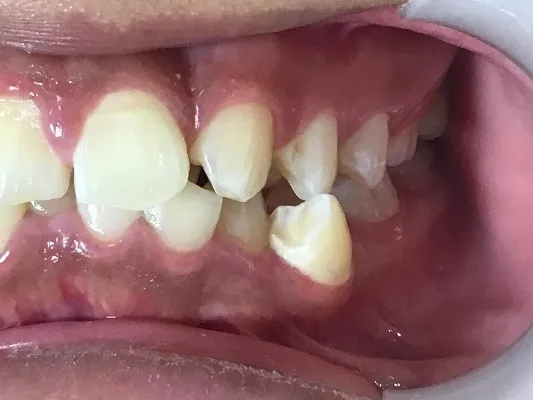

今回は他院さんでインビザライン矯正治療を受けていた患者様を引き継いで当院でインビザライン治療を継続した症例をご紹介致します。

今回はマウスピース矯正を主軸にした矯正ですが、一部ワイヤー矯正も併用して改善しております。

マウスピース矯正のみしか行っていない歯科医院では対処しきれない場合もあり、ワイヤー矯正とマウスピース矯正どちらも行える歯科医院で矯正治療を始めることがきれいな歯並びに近づける方法です。